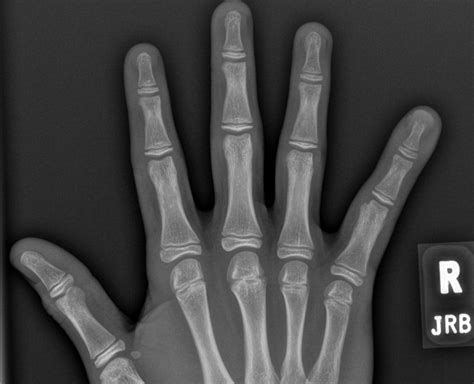

When you visit a healthcare professional, the diagnostic process is usually straightforward. The physician will perform a physical examination to check for stability and nerve function. To confirm the diagnosis of a distal phalanx fracture, the doctor will order an X-ray. Radiographic imaging is crucial because it allows the medical team to see the exact location and pattern of the break.

X-ray Imaging Confirms the fracture site and determines if surgery is needed.